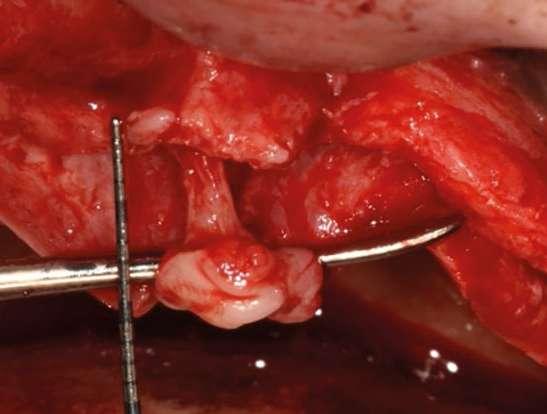

éste ha dado mejores resultados en regeneraciones anteriores y en sensaciones posteriores de los pacientes2. La lateralización del paquete vasculo-nervioso nasopalatino es, por tanto, aconsejable (Figura 5).

Una vez expuesto todo el tejido observamos zonas con grosores de 2 mm o incluso menos (Figura 6). La primera maniobra que realizaremos es la elevación de seno maxilar. La mayor modificación que aplicamos en esta técnica es la posición de la ventana y cómo acceder al seno. Accederemos al seno con rascadores óseos situándonos más en la zona anterior del mismo con un abordaje por la zona canina (posible en casos de neumatización extrema) (Figura 7).